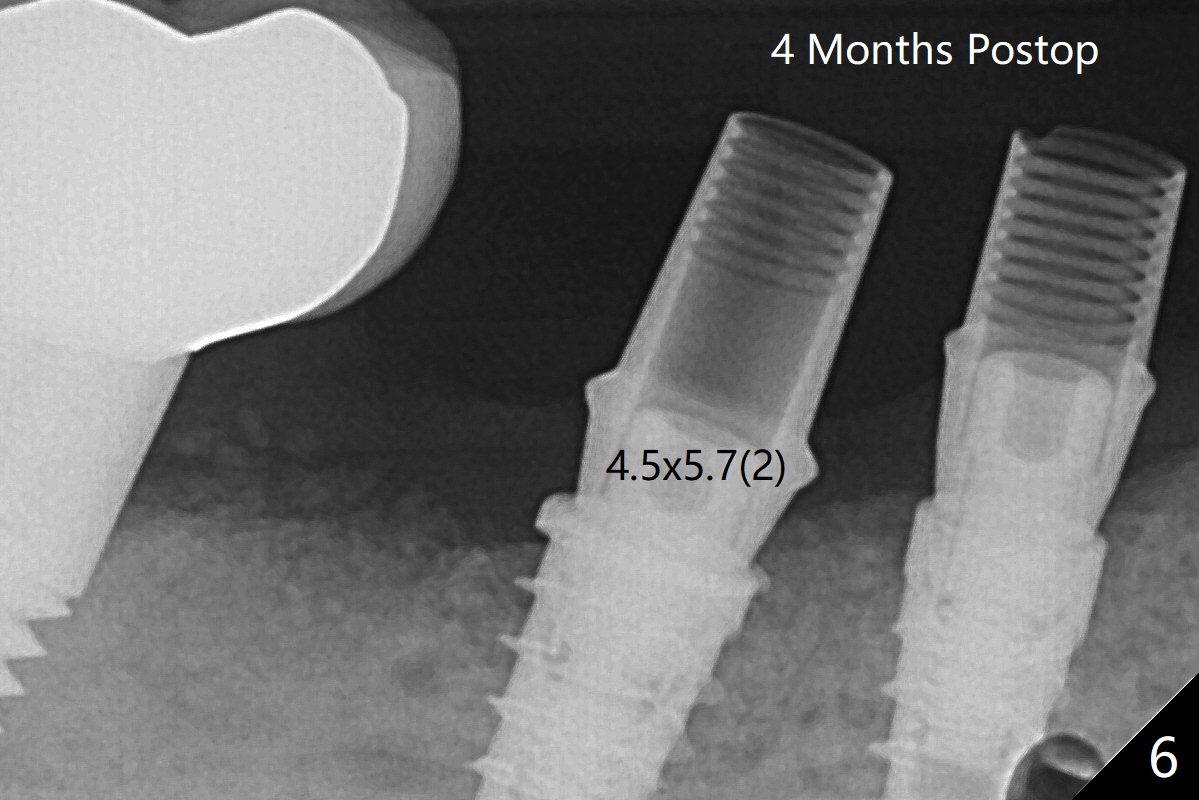

术后四个月6放置基台后(图六),制作连体5,6牙冠,垫高(打开咬合),近中衬里,推4,关闭3,4之间间隙(图三)。6植体远中第一个螺纹好像暴露。